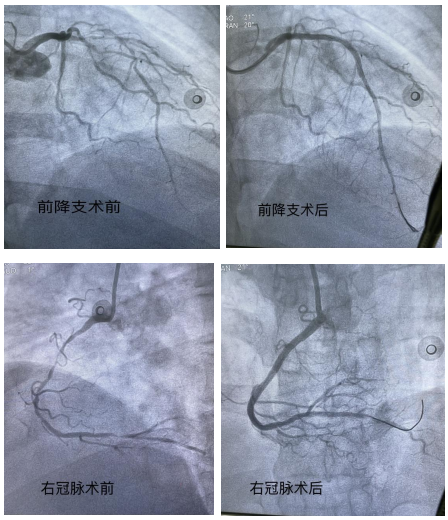

为确保患者安全,詹小娜前往急诊等候急救车。在接到患者后,她第一时间为患者进行冠脉造影检查,显示患者前降支、回旋支及右冠状动脉均存在超过90%的严重狭窄,且病变弥漫,斑块不稳定,为高危“三支病变”。詹小娜立即向患者及家属解释,这种情况下心肌处于严重缺血状态,随时可能因恶性心律失常导致猝死。经过患者及家属同意后,詹小娜随即为患者施行紧急介入治疗,开通堵塞血管,术后观察3天,患者在走廊活动已完全无症状,目前已平安出院。